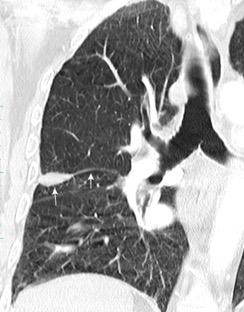

VIH+. 1 mes antes derrame pleural en el curso de una

infección